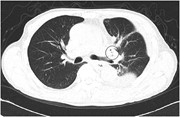

Fatal broncho-pulmonary artery fistula after lobectomy for lung cancer

Jiro Abe and others

Journal of Surgical Case Reports, Volume 2015, Issue 9, September 2015, rjv110, https://doi.org/10.1093/jscr/rjv110